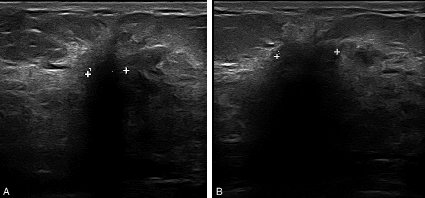

Figure 20.9. A, B Image échographique suspecte d’un cancer du sein (contours flous, irréguliers, grand axe perpendiculaire à la peau, cône d’ombre postérieur)